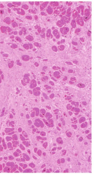

How can you tell that this heart and histological stain are from a patient who had Arrhythmogenic Right Ventricular Cardiomyopathy?